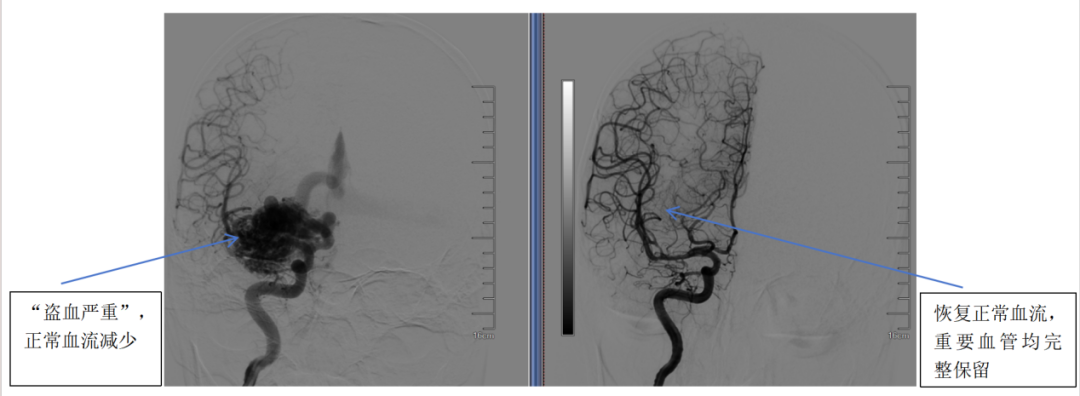

(图B:DSA全脑血管造影)

术后复查CTA显示畸形血管全部切除,复查DSA显示血流恢复正常,重要血管结构均完整保留。经康复观察,患者无任何并发症,头痛与癫痫消失,精神与记忆恢复正常。

CTA血管造影检查:可以静态显示血管,如图A;

DSA全脑血管造影:比CTA更精确,且可以动态显示血流,确诊“金标准”,如图B。